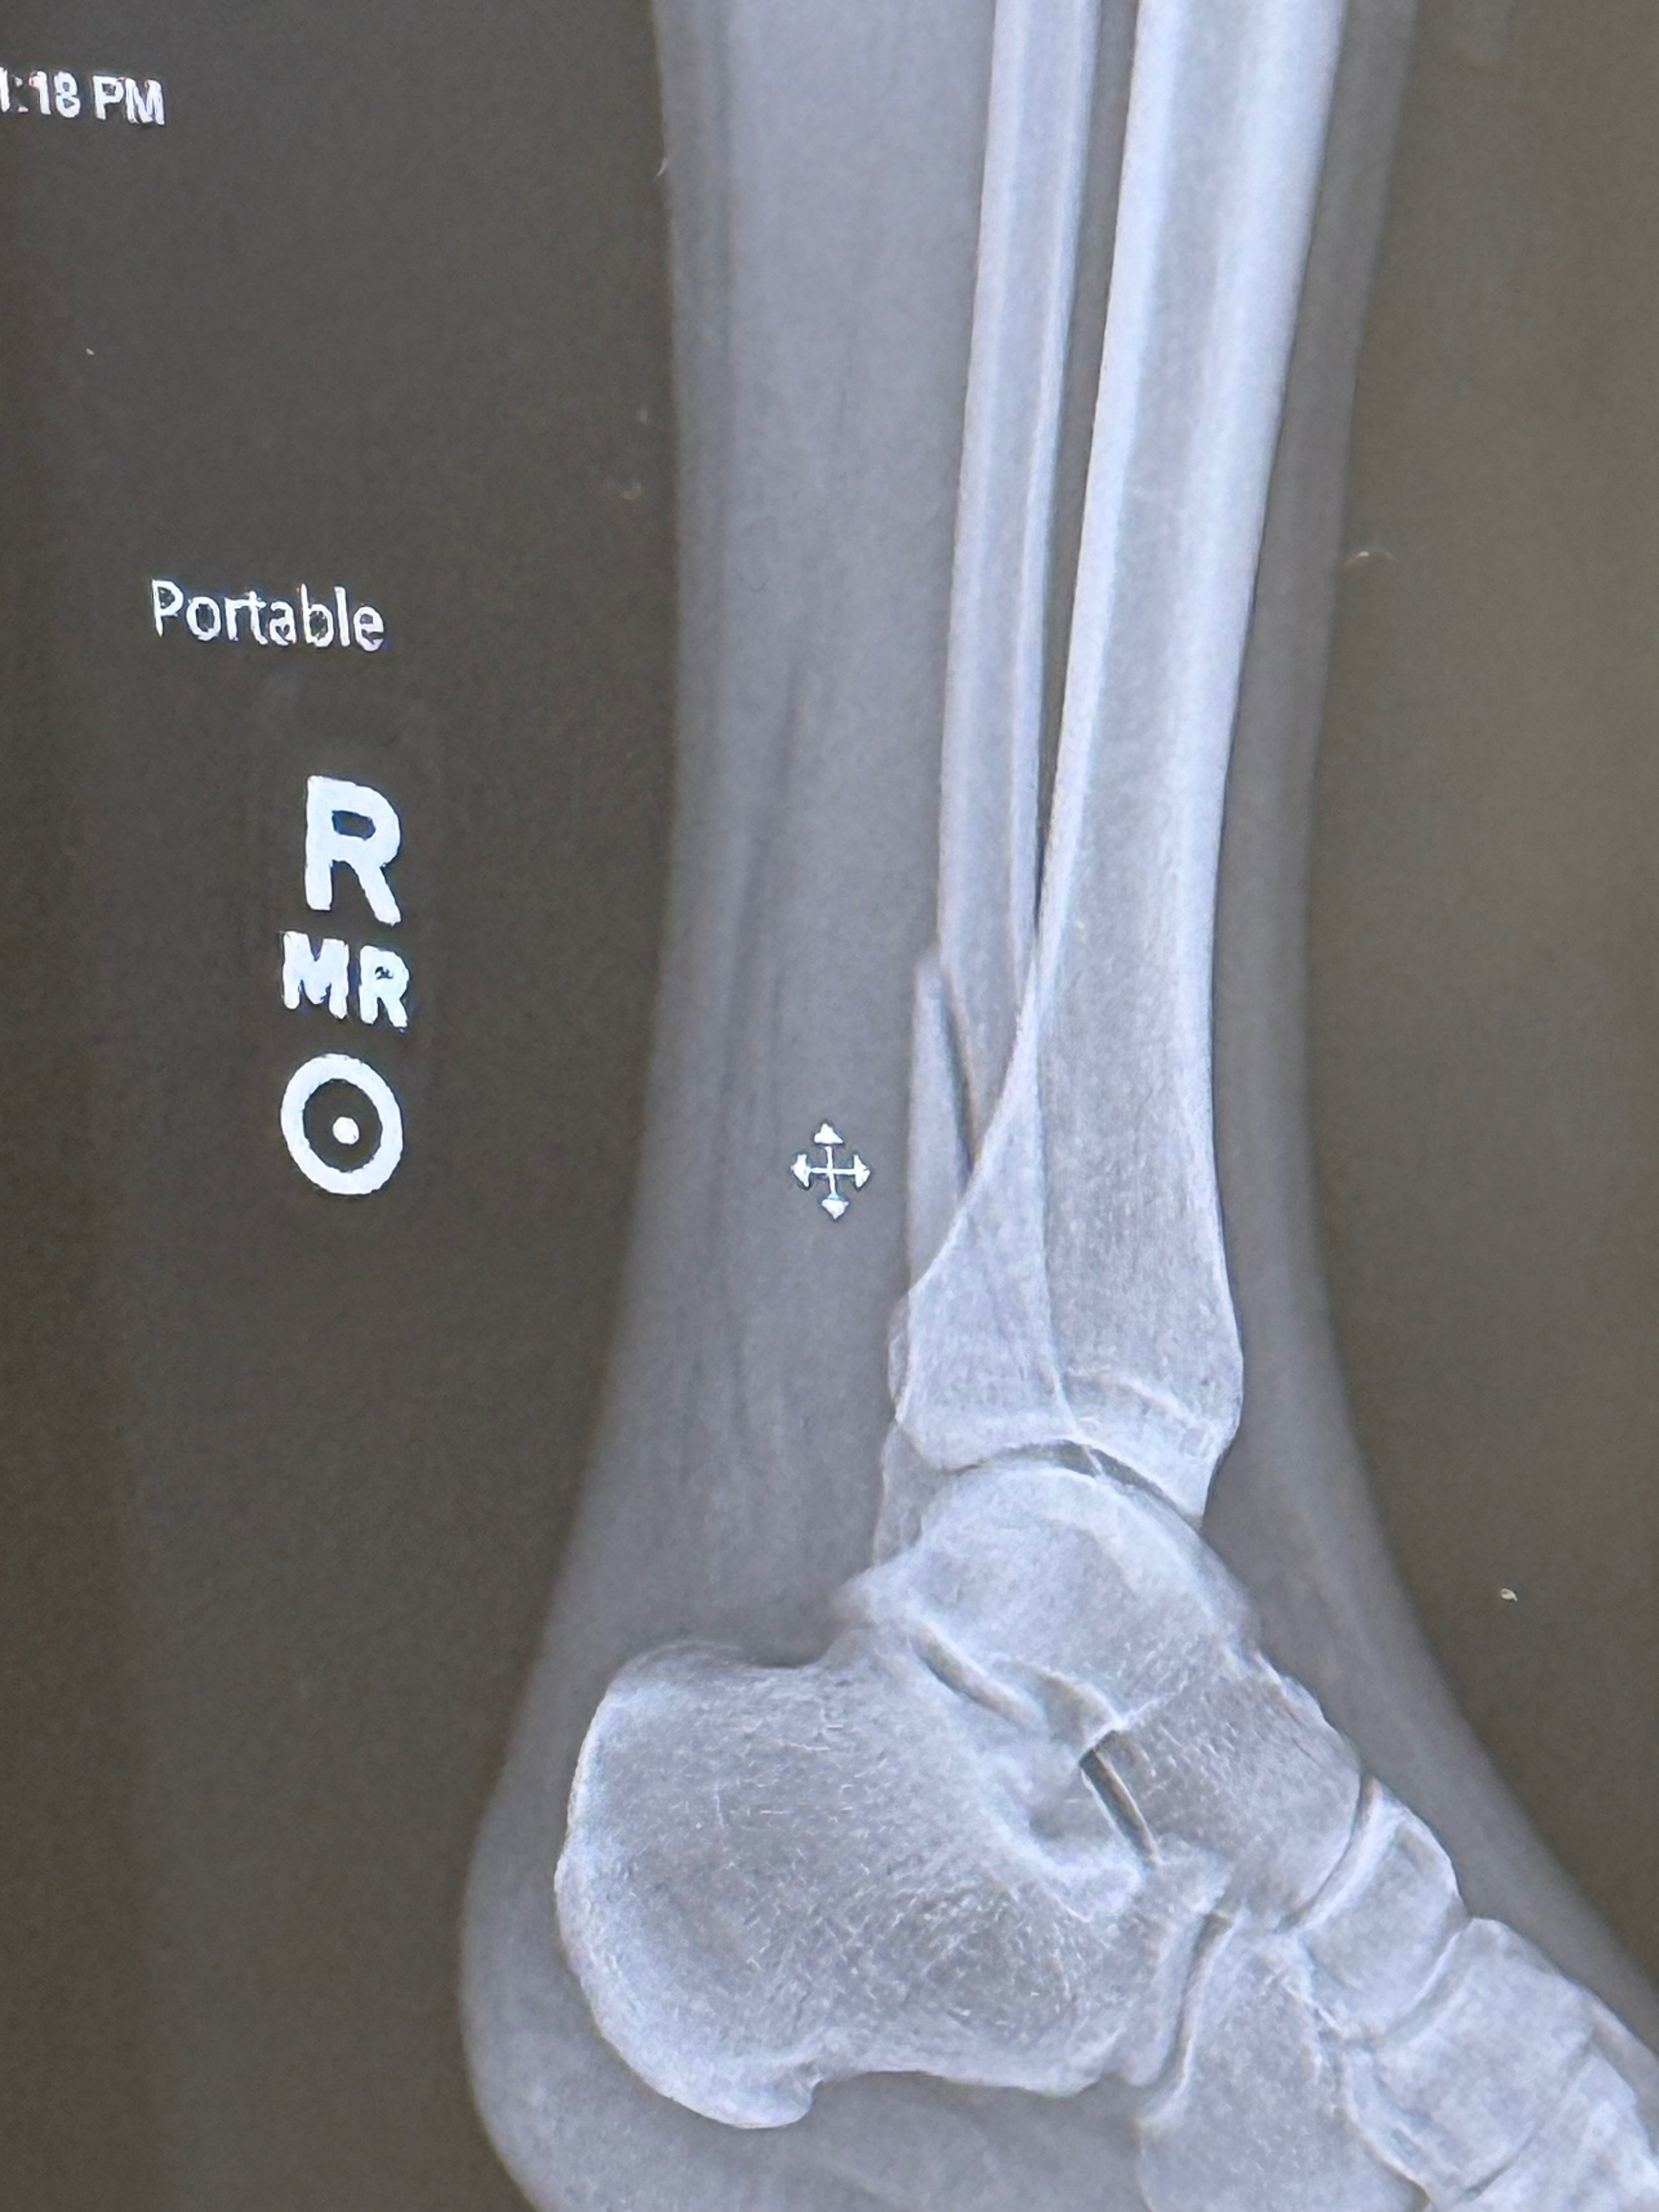

Recently, during a bull riding event, I suffered a serious accident that resulted in a broken ankle. I had to undergo surgery, and now I am in recovery. Unfortunately, this injury has left me unable to work for the time being, which has been very difficult because I have always depended on my own hard work to support myself.

Recentemente, durante uma competição de montaria em touros, sofri um grave acidente que resultou em uma fratura no tornozelo. Tive que passar por uma cirurgia e agora estou me recuperando. Infelizmente, essa lesão me deixou impossibilitado de trabalhar por enquanto, o que tem sido muito difícil, pois sempre dependi do meu próprio trabalho para me sustentar.